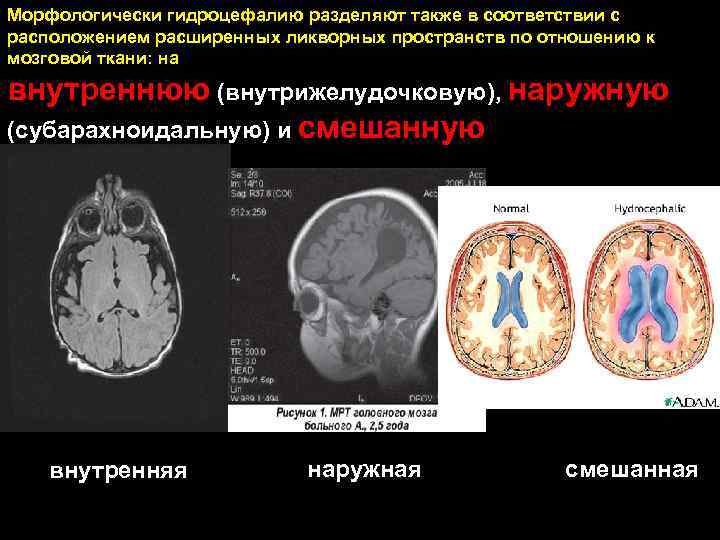

Признаки умеренно выраженной наружная

Признаки умеренно выраженной наружная 113 фото